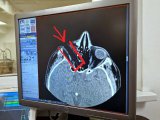

Чаллыда уникаль операция ясалды

5нче шәһәр хастаханәсе офтальмологлары 35 яшьлек ир-атның күзен саклап калды.